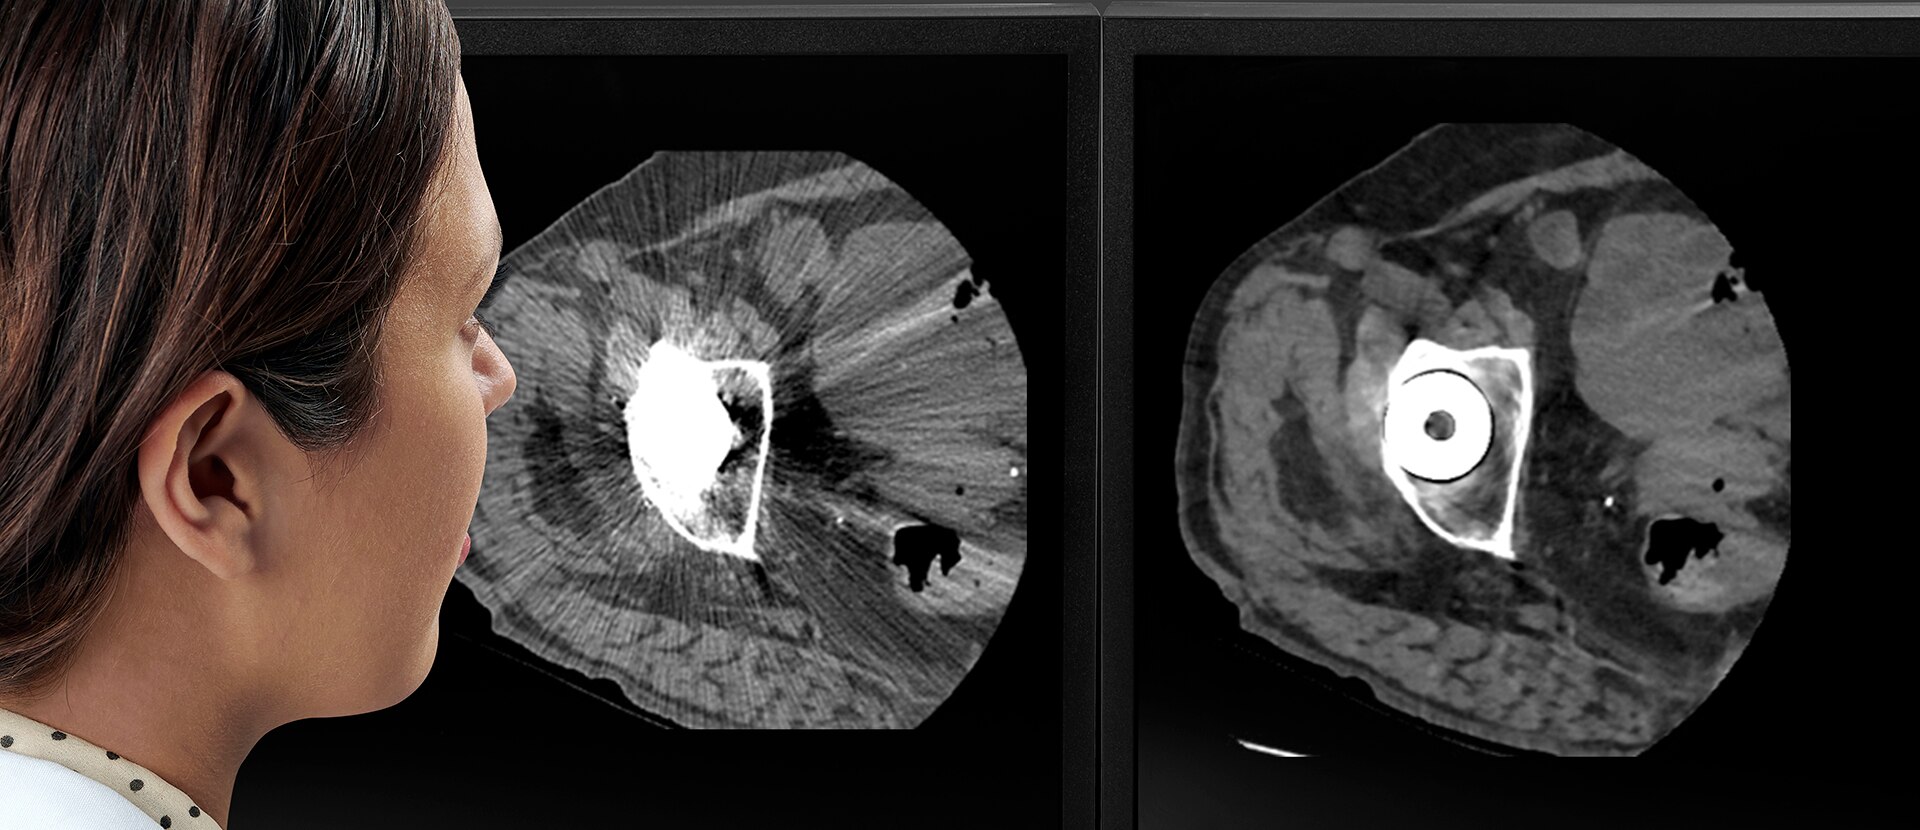

GEHC Revolution Maxima Product Web Page Post Scan Image 1

Findings you can clearly dictate

Your CT experience doesn’t end with the generation of a high-quality image. You also need intelligent applications that continue to support you once those images reach the reading room. We’ve developed a collection of smart applications for cardiac, stroke, oncology and metal artifacts that do just that.

Smart MAR

Single acquisition metal artifact reduction.